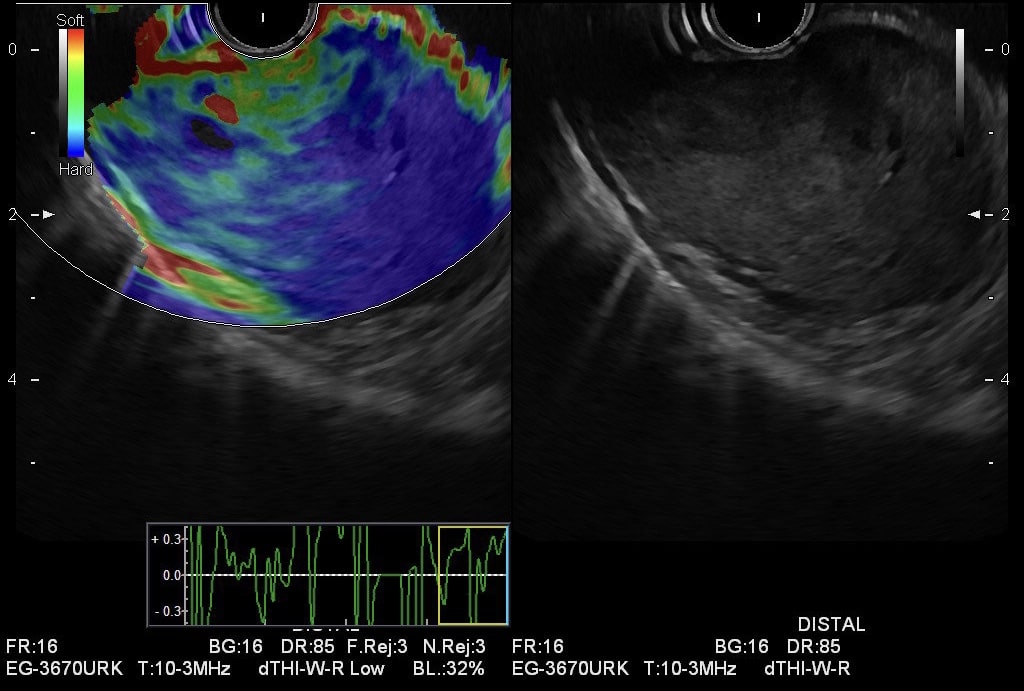

54-jährige Patientin mit GIST des Magens. Die Patientin wurde mit einer transfusionspflichtigen Anämie zugewiesen, klinischerseits wurde Teerstuhl vernommen. Bereits in der Abdomensonographie war eine Raumforderung im Bereich des Magens auffällig. In der daraufhin durchgeführten Ösophagogastroduodenoskopie sahen wir subkardial einen großen exulzerierten, submukösen Tumor. Endosonographisch stellte sich die Raumforderung scharf begrenzt dar, etwa 5 x 4 cm, zentral leicht inhomogen mit kleinsten echofreien Anteilen, insbesondere im Randbereich mit starken Gefäßen. Eine laparoskopische Magenteilresektion schloss sich nach Abschluss des Stagings an, der Tumor wurde vollständig reseziert. Die pathologische Aufarbeitung bestätigte die Verdachtsdiagnose eines gastrointestinalen Stromatumors.